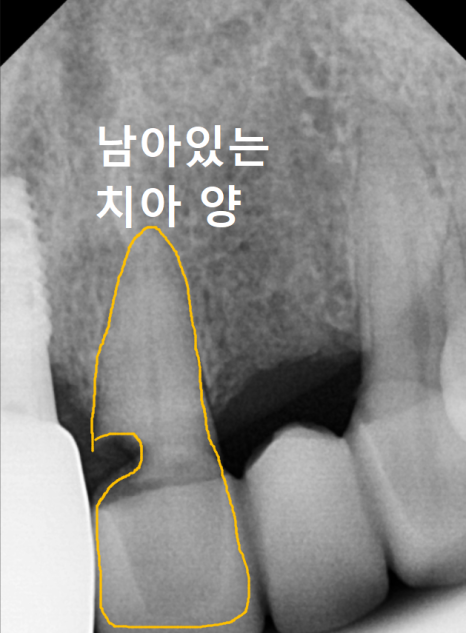

기존 브릿지를 제거하고

내부 상태를 확인했습니다.

예상대로 음식물 찌꺼기와 오염이 심각했지만,

여기서 불행 중 천만다행인 사실...

230516

남은 치아의 양이 적당하여

발치는 피할 수 있는 상황이었어요.

저는 환자분께 기존의 연결된 형태가 아닌,

각각의 치아를 독립적으로

치료하는 방식을 제안 드렸습니다.